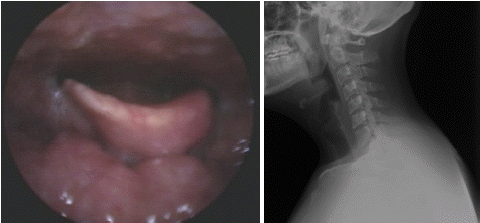

특이병력이 없던 28세 남자환자가 2일 전부터 시작된 목통증과 호흡곤란을 주소로 내원하였다. 침 흘림(drooling), 38도 초반의 발열, 삼킴시 통증을 호소하였다. 다음은 후두경 및 경부 단순방사선검사 소견이다. 이 질환에 대한 설명으로 옳은 것은?